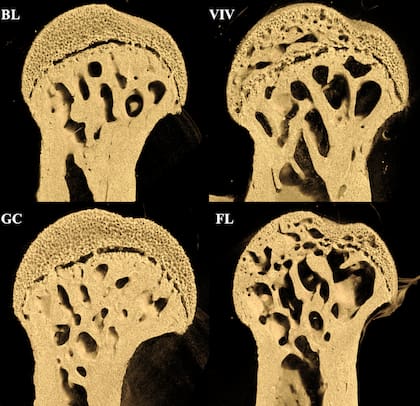

Los investigadores analizaron muestras de huesos de ratones hembra de 16 semanas expuestos a 37 días en órbita terrestre baja a bordo de la Estación Espacial Internacional (EEI). Los resultados mostraron una disminución considerable en la densidad del fémur, pero no en la columna vertebral. Esto sugiere que la pérdida está directamente relacionada con la descarga mecánica en ausencia de gravedad.

El estudio indicó que el hueso cortical y el esponjoso de la cabeza femoral son los más afectados. En humanos, la columna lumbar soporta gran parte del peso, mientras que en roedores la distribución del peso recae principalmente en sus patas traseras. La investigación reforzó la teoría de que la microgravedad afecta principalmente los huesos de soporte de peso, en lugar de causar una pérdida ósea generalizada debido a la radiación espacial.